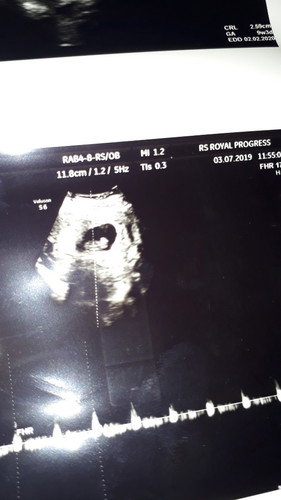

Semalem mau pipis liat cd ada flek,,, ya Allah pikiran jd kacau, lgsg aja ke bidan, bidan pun ga bs cek karna usia kandungan ku baru 9w blm terdengar suara jantung nya,,, dan di rujuk lah ke rs hari ini... alhamdulilah pas di usg janin dan jantung nya bagus, jd lega... kata dokter jgn banyak pikiran stres yg menyebabkan terjadi nya keguguran... tp sih bbrp kali ada hub sm suami sperma nya masuk ke dlm, mgkn saja karna itu... Bunda dan mommy yg disini minta saran nya dong biar ga stres mikirin masalah hidup bagaimana?